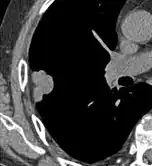

Thin slice and maximal intensity projection of a lung nodule, the latter better visualizing vascular convergence.[9]

• Vascular convergence is where vessels converge to a nodule without adjoining or contacting the edge of the nodule, and is mainly seen in peripheral subsolid lung cancers.[9] It reflects angiogenesis.[9]